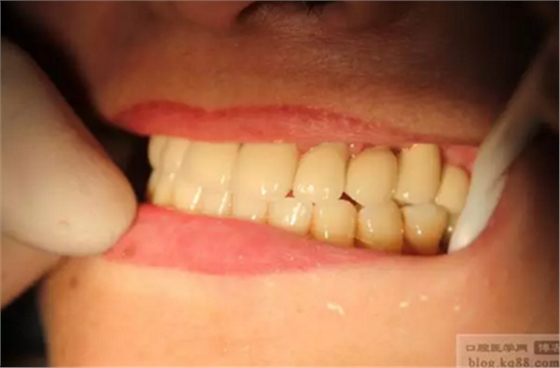

雙側(cè)種植牙分別做成連冠、前牙做成單冠,左下6、7連冠,(戴牙后照片)